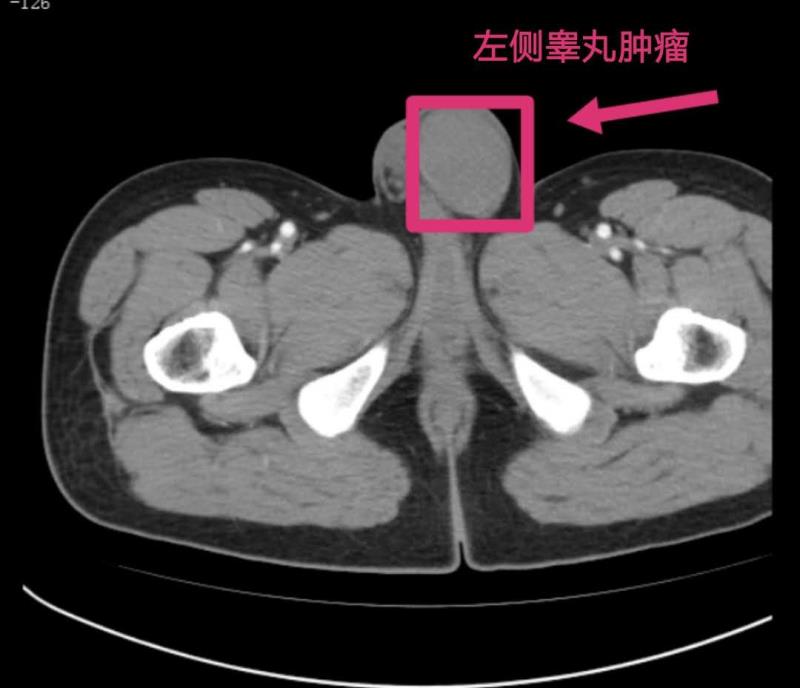

经检查发现,患者左侧*丸睾**增大,有肿瘤。在为其进行全麻下*丸睾**探查+*丸睾**根治性切除术后,病理结果确诊刘先生患的是*丸睾**精原细胞瘤,为*丸睾**恶性肿瘤。通过一周的精心护理,目前,刘先生已顺利出院。